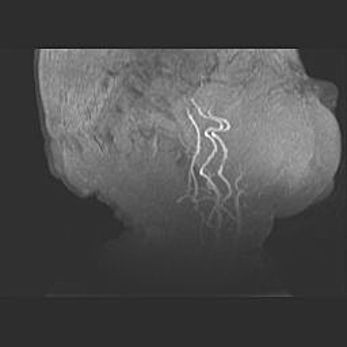

Подострая гематома правой гемисферы мозжечка.

Наружная гидроцефалия.

Возраст: 15 дней

Вес: 3100 г

Пол: женский

Окружность головы: 37 см

Срок гестации: 35-36 недель

При открытой наружной форме гидроцефалии у новорожденных расширяются и переполняются субарахноидные пространства.

Кровоизлияния в мозжечок имеют две клинико-анатомические формы: полушарные гематомы и кровоизлияния в червь.

К появлению этой патологии может привести: повреждения головного мозга, возникающие в результате асфиксии и гипоксии плода при беременности, или травмы во время родов. Редко гематома мозжечка может быть результатом первичной коагулопатии и сосудистой мальформации, диссеминированном внутрисосудистом свертывании, изоиммунной тромбоцитопении.